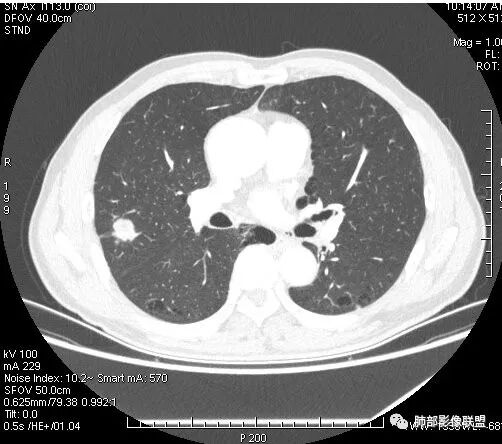

患者右上肺占位,内部强化不均,有空泡,有血管穿过,血管聚集现象,似有胸膜牵拉,考虑恶性

右肺上叶后段占位病灶,病灶不规则,周围胸膜线性牵拉,病灶部分周围有晕,病灶内见不规则空洞,未见明显引流支气管,长毛刺,多分叶、肿块边缘部分L型,可见血管直接供养。增强见点状坏死、病灶内血管。综上考虑恶性可能性大,鉴别隐球菌。

右肺上叶结节,浅分叶膨隆,边缘可见胸膜牵拉及血管集束,不规则厚壁空洞,不均匀强化,血管进入病灶,边缘毛燥,考虑低分化腺癌,鉴别隐球菌。

来个不一样的,小病灶近心端空洞,分叶,毛刺软,长,收缩力差,强化明显,血管走形自然,无明显卫星灶,先考虑炎性,肉芽肿炎,隐球菌可能性大,不排除肿瘤,需要活检

右肺团块影,深分叶,有毛刺,但毛刺偏软。团块附近有血管走行,穿过。血管增粗,僵直。空洞近心,团块周围似有卫星灶。良,恶性征象都有;按可能性排序:隐球,结核,腺癌。

右肺结节,分叶、长短毛刺,边缘略膨隆,胸膜牵拉,血管进入病灶,收缩力较弱,有血管聚集征,洞壁尚规整,低强化,坏死边缘规整。考虑炎性,隐球,鉴别腺癌。

晨读,右肺上叶结节,边缘膨隆、分叶,部分边缘有平直,可见多发毛刺及胸膜牵拉,牵拉线清秀,收缩力弱,内密度不均,可见片状低密度影及空洞,增强后不均匀强化,血管集束,考虑良性,肉芽肿性结节,鉴别腺癌

晨读:双肺胸膜下多发小气囊,大小不一,右肺结节,内部可见小空洞,洞壁光滑,厚薄不一,偏心性生长,近段血管束增粗,有分叶,毛刺(软),有晕征,平扫密度尚可,增强后不均匀强化,可见低密度坏死,及部分血管穿行,体检发现,考虑恶性:腺癌,鉴别炎性结节

晨读:右肺中叶结节,浅分叶,边缘膨隆,胸膜牵拉,不规则偏心厚壁小空洞,空洞壁可见低密度坏死,不均匀强化,血管进入病灶,边缘毛燥,考虑鳞癌。鉴别肉芽肿

右肺上叶结节,边界清,有分叶,厚壁空洞,强化后见坏死区,血管进入病灶,考虑结核。

右上叶结节,轻分叶,结节有长短不一毛刺,结节周围GGO边界清,有血管集束征,肺窗结节周围似可见卫星灶,可见鬼脸征,良恶性征象都有,但GGO边界清,浸润性腺癌耍考虑,临床症状轻微,体捡发现,似可见卫星灶和鬼脸征,炎性肉芽肿TB或隐球菌要鉴别。